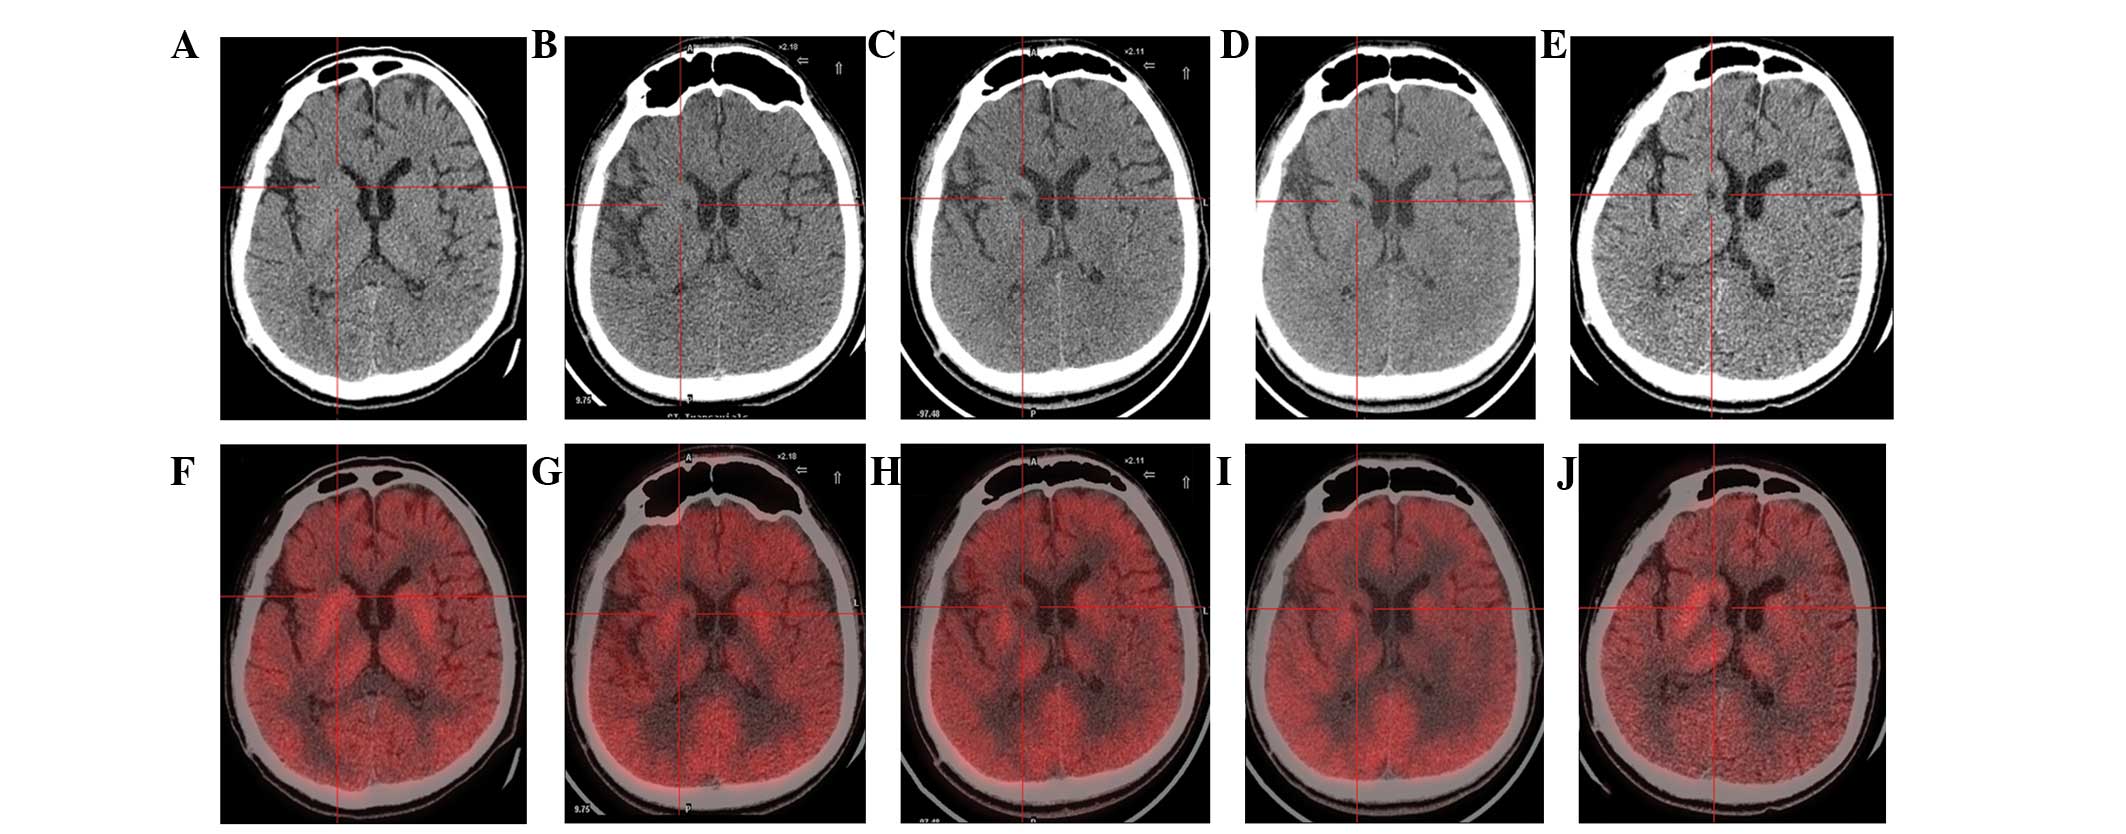

(A) 術前CT顯示腦萎縮。

(BE)術后1年、2年、3年、4年CT與術前相比均無明顯變化。

(F)術前18F-氟脫氧葡萄糖 (FDG) PET 掃描顯示,整個大腦皮層FDG攝取彌漫性減少,細胞核FDG攝取相對高于其他區域。術前1天,豆狀核和丘腦的標準化攝取值 (SUV) 平均值/最大值分別為4.3/5.8和3.3/4.5。

(GJ) 神經干細胞移植治療后分別 1、2、3 和 4 年的 18F-FDG PET 掃描顯示,雙側植入部位的豆狀核和丘腦對 18F-FDG的攝取增加(紅十字)與植入前相同部位進行比較。 豆狀核和丘腦的SUV*平均值/最大值在 1、2、分別是術后3年和4年。 該結果表明移植后葡萄糖代謝比移植前稍高。

CT(圖1b-e)和MRI(圖2b-d)掃描顯示4年隨訪期間沒有顯著變化。 手術前1天(圖1f)和手術后1、2、3和4年(圖1g-j) 獲得18F-FDGPET掃描。術后雙側植入部位豆狀核和丘腦18F-FDG攝取值較術前增加。這一結果表明,自移植以來,葡萄糖代謝逐年略有增加。